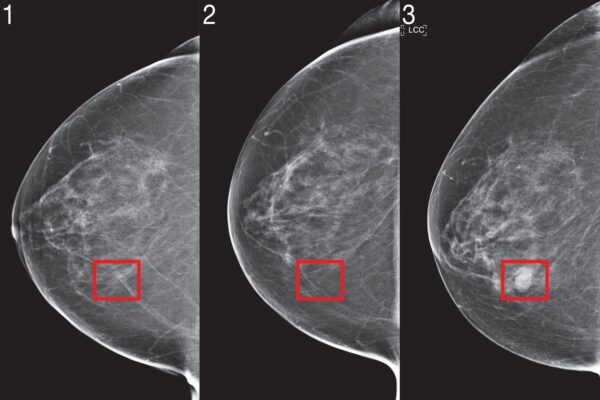

Recently, deep learning mammography-based risk models have shown promising performance. To bring this technology to the clinic, the team identified three innovations they believe are critical for risk modeling: jointly modeling time, the optional use of non-image risk factors, and methods to ensure consistent performance across clinical settings.

Although the current model doesn’t look at any of the patient’s previous imaging results, changes in imaging over time contain a wealth of information. In the future the team aims to create methods that can effectively utilize a patient’s full imaging history.

In a similar fashion, the team notes that the model could be further improved by utilizing “tomosynthesis,” an X-ray technique for screening asymptomatic cancer patients. Beyond improving accuracy, additional research is required to determine how to adapt image-based risk models to different mammography devices with limited data.